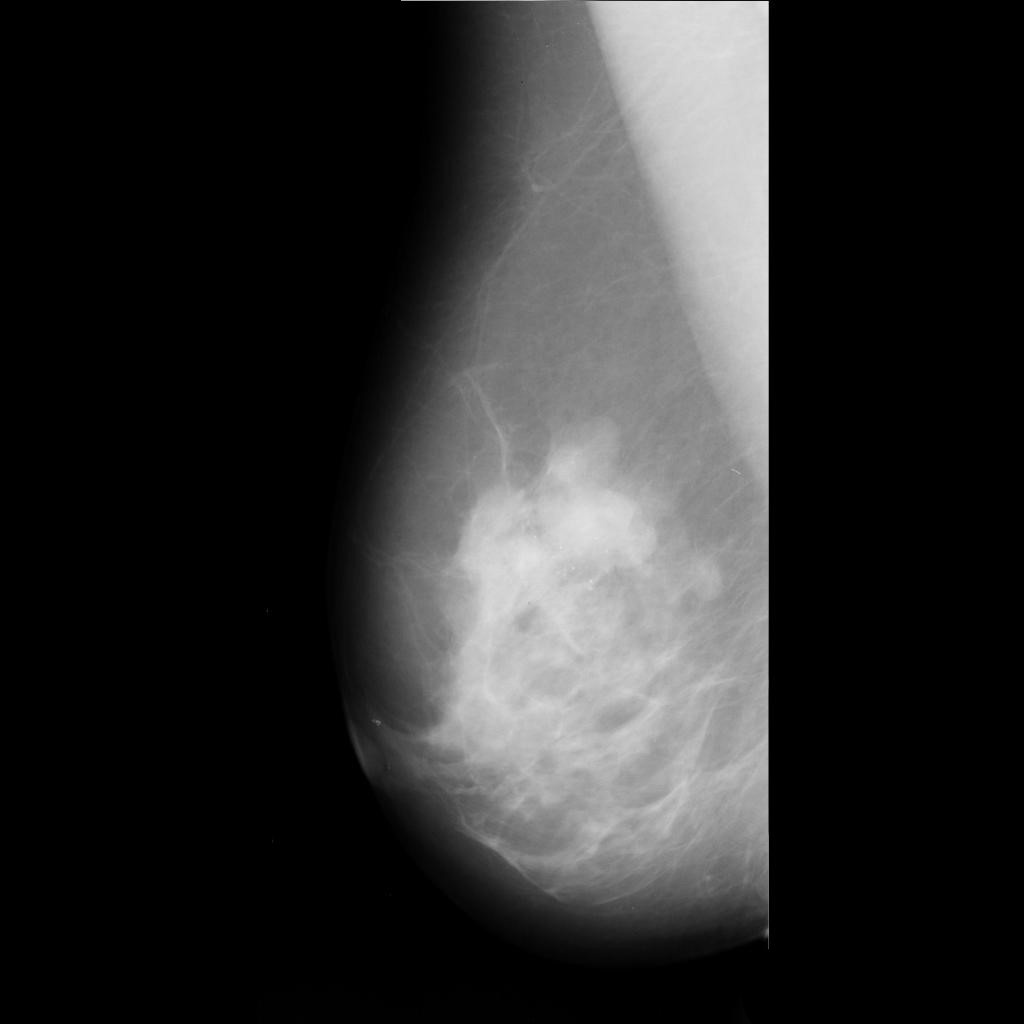

malignant